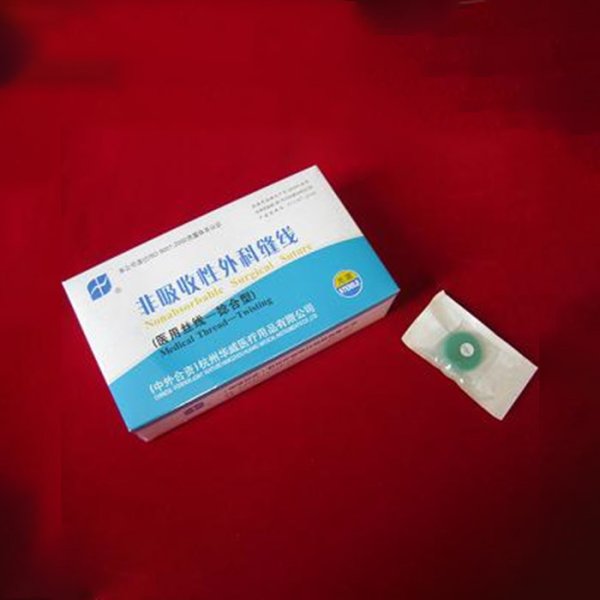

非吸收性外科縫線1

非吸收性外科縫線2